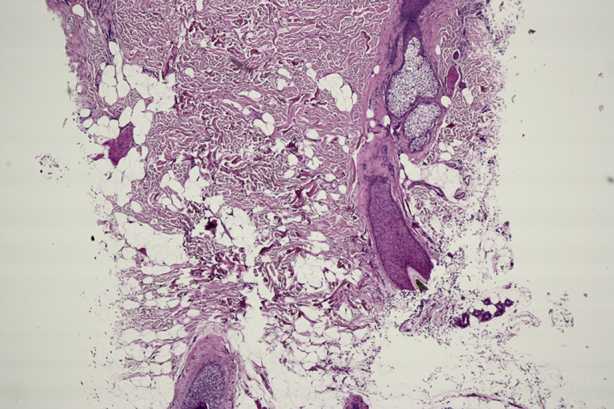

Fig 2.

Histopathologic stain with hematoxylin-eosin stain. Note thickening of subcutaneous tissue.

On physical examination, the patient had a 1- to 2-cm scalp hair length with evidence of predominantly nonscarring alopecia diffusely over the scalp. Palpation of the scalp found marked bogginess and thickening (Fig 1) that instantly returned to normal after releasing pressure. No rash, scale, or evidence of trauma was noted on the head. Computed tomography scan found increased subcutaneous tissue of the scalp measuring 14 mm in thickness, more prominent at the vertex of the scalp. There was no trauma to the skull or cerebrospinal fluid leak. Hematoxylin-eosin stain of the scalp found decreased hair follicle density and a pauci-inflammatory process with thickening of collagen bundles and increased space between bundles suggestive of edema (Fig 2). No scar or mucin was present, and 1 anagen follicle was noted (Fig 3).

Histomorphologic criteria of LA and LS include a thickened layer of subcutaneous fat with variable disruption of fatty architecture, no visible panniculitis or lipoma, the absence of inflammation, and normal hair follicles and adnexae.5 Diagnostic modalities include computed tomography scan, magnetic resonance imaging, and histopathology. Normal mean thickness of the scalp is between 5 and 8 mm, and pathologic scalp thickness in LA/LS is between 9 and 19 mm.5 Our patient's scalp thickness was 14 mm. Histology usually finds a normal epidermis and dermis as well as a hyperplasia of the subcutaneous adipose tissue.